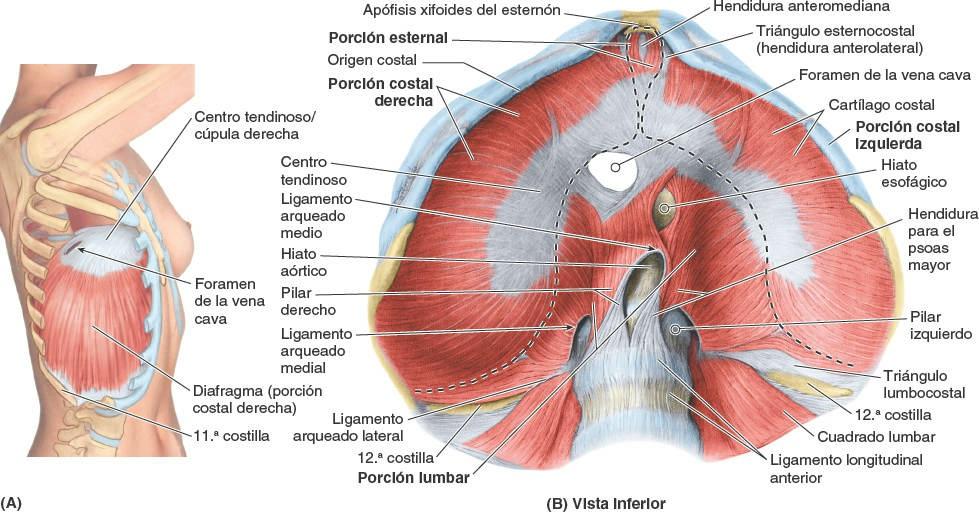

Анатомия диафрагмы и треугольника Бохдалека

Раздел: Визуальный дайджест